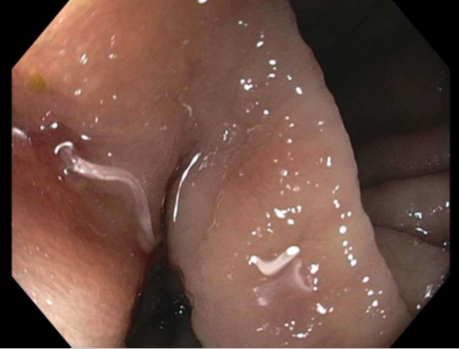

The bronchoscopy revealed a bloody fluid admixed with clots which was clinically consistent with diffuse alveolar hemorrhage. The roundworms depicted above were identified in both the BAL and stool O&P exam. Based on the presence of the short buccal cavity and the prominent genital primordium and the absence of eggs, the identification of Strongyloides stercoralis was made. Given the large amount of larvae present in both the lungs and gastrointestinal tract, the patient was diagnosed with a strongyloidiasis hyperinfection.

In the laboratory, the diagnosis of S. stercoralis is most often made by an ova and parasite exam of the stool, duodenal fluid, sputum or BAL specimens (Image 1). Most commonly the rhabditiform larvae are present and are identified by the presence of a short buccal cavity and prominent genital primordium (Image 2). These two features are helpful in distinguishing S. stercoralis from hookworms (Ancylostoma spp. and Necator americanus) which have a longer buccal cavity and indistinct genital primordium. The eggs of these two nematodes are also very similar, although typically S. stercoralis eggs hatch before they are passed in stool specimens. S. stercoralis can also be visualized on H&E histology sections in the crypts of intestinal biopsies where the adult female measures up to 2.2 mm in length. Finally, serologic testing can be helpful when there is a high suspicion of disease in the face of multiple negative stool exams, but cannot distinguish between a current or past infection. Most patients do not remember a specific exposure and prevention includes wearing gloves and shoes when handling or walking on soil that may contain contaminated fecal material. Treatment options for an acute or chronic S. stercoralis include a short course of ivermectin or albendazole. In the case of disseminated infection, ivermectin should be given until stool and sputum exams are negative for 2 weeks. In the case of our patient, she was started on ivermectin, but succumbed to the disease due to extensive pulmonary hemorrhage.